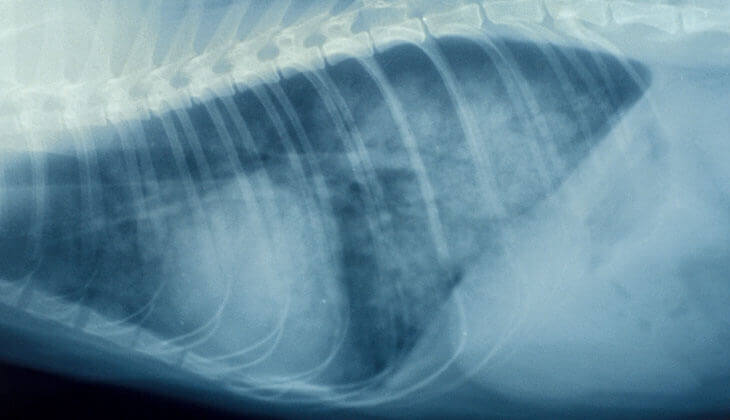

FURTD is a complex disease. There is a considerable overlap between the clinical signs seen with other agents that can cause FURTD. However, in studies with cats in which B. bronchiseptica was known to be the only causative agent, clinical signs included fever, sneezing, nasal discharge and often coughing (usually starting around 3-5 days after infection). In most cats the disease is usually mild, and signs normally disappear after about 10 days. However, in some cats, particularly younger animals, it can develop into bronchopneumonia and be life-threatening. Some cats may become long-term carriers and recovered cats have been shown to shed Bb at least 19 weeks after initial exposure.